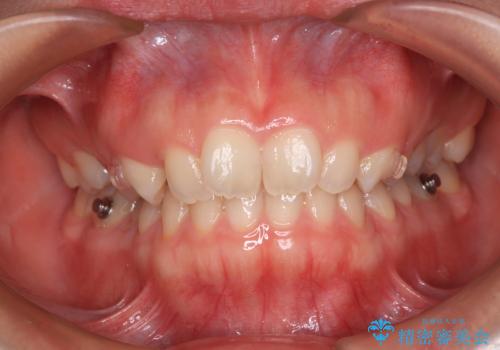

- 上の前歯が前方に飛び出していることを気にして来院された患者様です。

奥歯の咬み合わせをチェックすると、上顎歯列が相対的に前方に位置しているため、補助装置を用いて上顎歯列を確実に後方に移動させ、インビザラインで歯列を整えて行くこととしました。

インビザライン単体でも同様の結果が得られる可能性がありますが、万が一奥歯がうまく後方移動できなかった場合、リカバリーが非常に大変となるため、事前に補助装置を併用して確実に結果が得られるように工夫をしています。